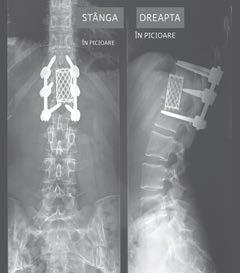

imaginez cu ochii minții ce se va întâmpla, nevenindu‑mi să cred în totalitate: chirurgul îmi va deschide toracele dintr‑o parte, pornind de la nivelul taliei, tăind apoi în spate, ca să ajungă la nivelul vertebrei rupte. Apoi va scoate fragmentele de os, precum și cele două discuri adiacente, după care va suda laolaltă trei vertebre și îmi va face șase găuri în șira spinării, ca să introducă șase tije metalice lungi de 7,5 centimetri. Cu un burghiu electric. Riscurile aferente procedurii mă îngrozeau: perforarea plă‑ mânului, paralizie, deces. Dar nu că aș fi avut de ales. Fragmentele de vertebră îmi apăsau pe membrana măduvei spinării. Orice șoc (chiar și numai dacă mă împiedicam pe scări) putea duce la o ruptură de membrană, paralizându‑mă de la mijloc în jos. Eram înspăimântată. Mă și vedeam pe masa

Rezultatul final (Nu, nu declanșez alarma de securitate la aeroport și, da, chestia asta rămâne în mine pentru totdeauna�)